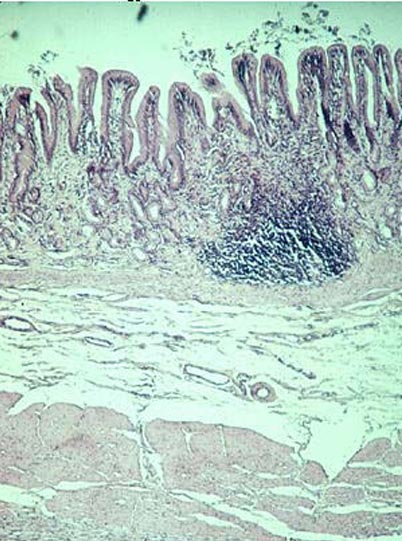

pyloric stomach